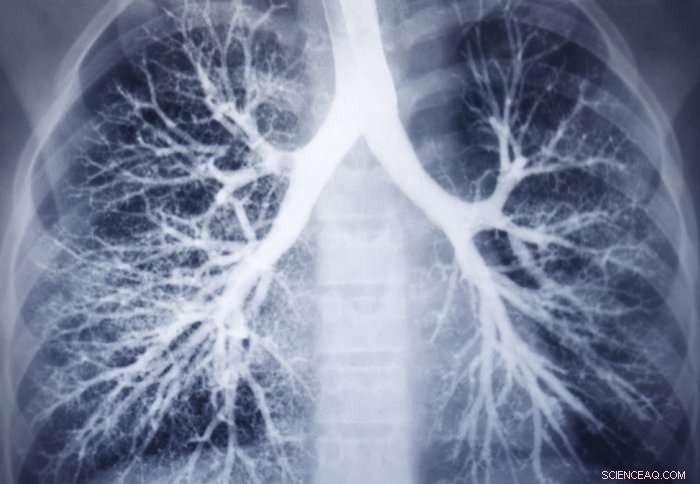

Nanomedicine could help patients with fatal lung conditions. Credit: Imperial College London

Metallic nanomolecules capable of carrying drugs to exactly where they are needed could one day help to treat patients with a fatal lung condition.

In PAH the blood vessels of the lungs constrict and thicken, increasing blood pressure and causing the right side of the heart to work harder and harder, until it eventually fails. The condition is rare but devastating and can affect people of all ages, including babies, young adults and the elderly. Patients in the late stage of the disease have few treatment options beyond transplant, with a mean survival time of around five years following diagnosis.